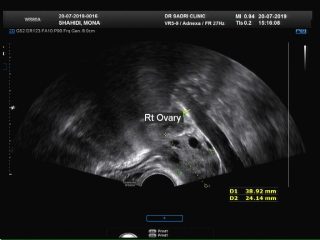

- 14 تصاویر سونوهیسترو در کلینیک سونوگرافی و رادیولوژی دکتر صدری و توضیح دکتر صدری در مورد آن

تصاویر سونوهیسترو در کلینیک سونوگرافی و رادیولوژی دکتر صدری و توضیح دکتر صدری در مورد آن